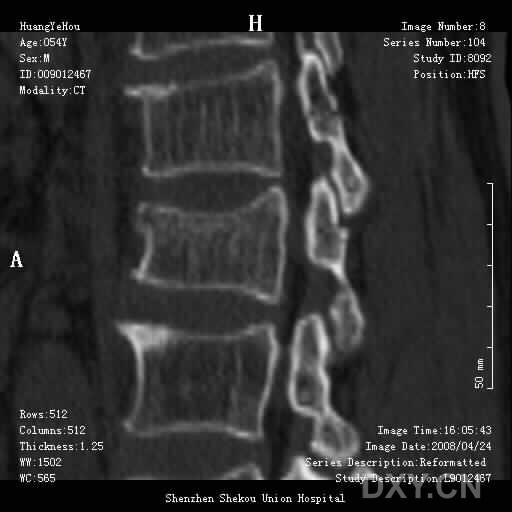

男,54岁,腰部外伤疼痛2小时!

1、腰3椎体压缩骨折

2、腰椎退行性变。

这么好的片子没见过 不知l2,l3椎板是否有问题 ,好象有线样低密度影

1.腰椎椎体压缩性骨折,  2. 退行性改变(局限性骨质密度增高.

前缘变窄;压缩骨折;椎体硬化征;退行性变